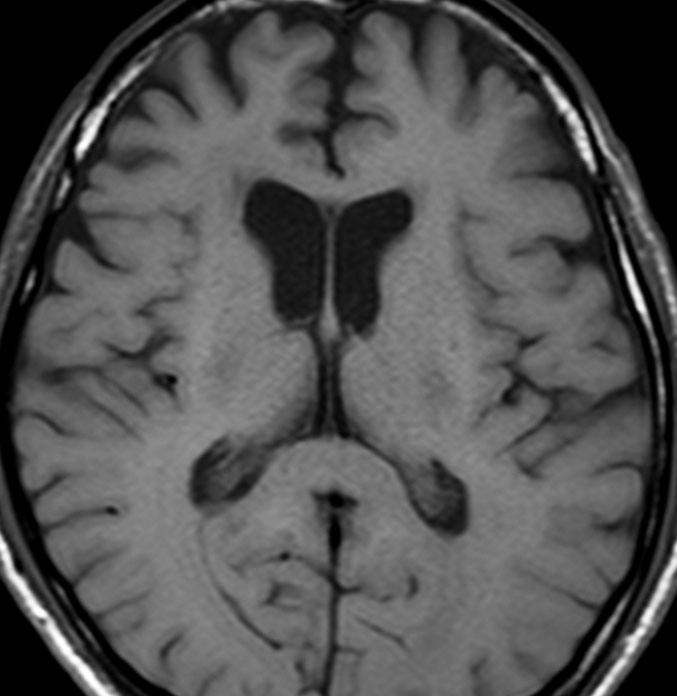

左側頭葉のびまん性星細胞腫です。左側のT1強調ガドリニウム像ではほとんど腫瘍は見えません。真ん中のT2強調画像でも見づらいです。右側のフレア画像で白くにじんでいるところに腫瘍があります。どこまでが腫瘍の境界なのかがはっきりしない腫瘍です。左の海馬(記憶の中枢)を侵し,とてもゆっくり大きくなるタイプで,この患者さんは10年以上治療をしないで経過を見ています。全摘出できない星細胞腫グレード2です。